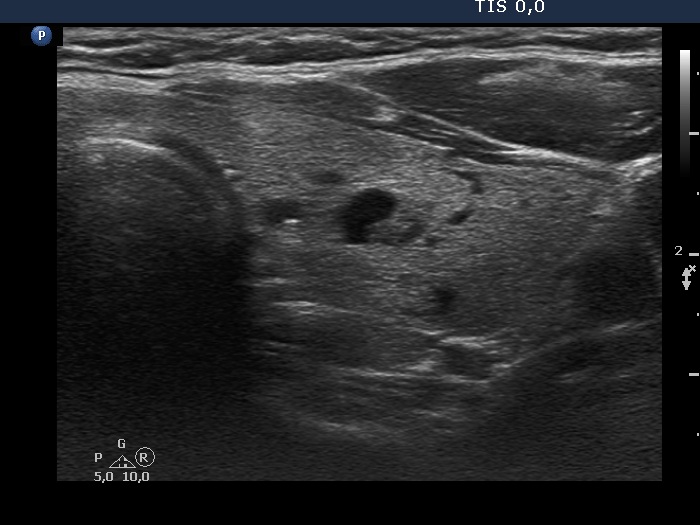

Comment. The judgement of several ultrasound characteristics is not easy in this case. First, the echogenicity of the nodule: echonormal and hypoechoic parts occur in roughly equally. The borders present undulation at the ventral and lower parts which can be regarded pathological. Finally, the intranodular echogenic figures are also difficult to judge.